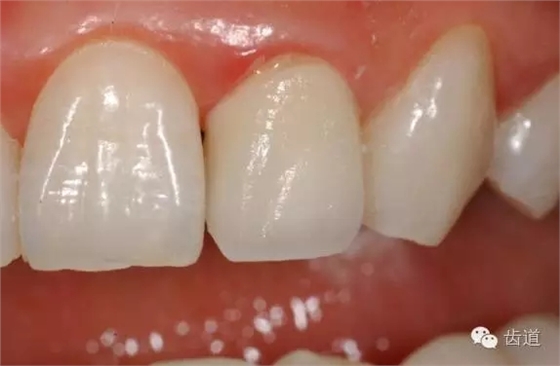

3、邊緣適合度(marginal adaptation): 冠邊緣與頸緣間隙<50μm

六)外形(contour):

符合生理要求及解剖特點(diǎn)

七)美觀(esthetics):

位置、形態(tài)、排列、色彩與鄰牙及整個牙列協(xié)調(diào)